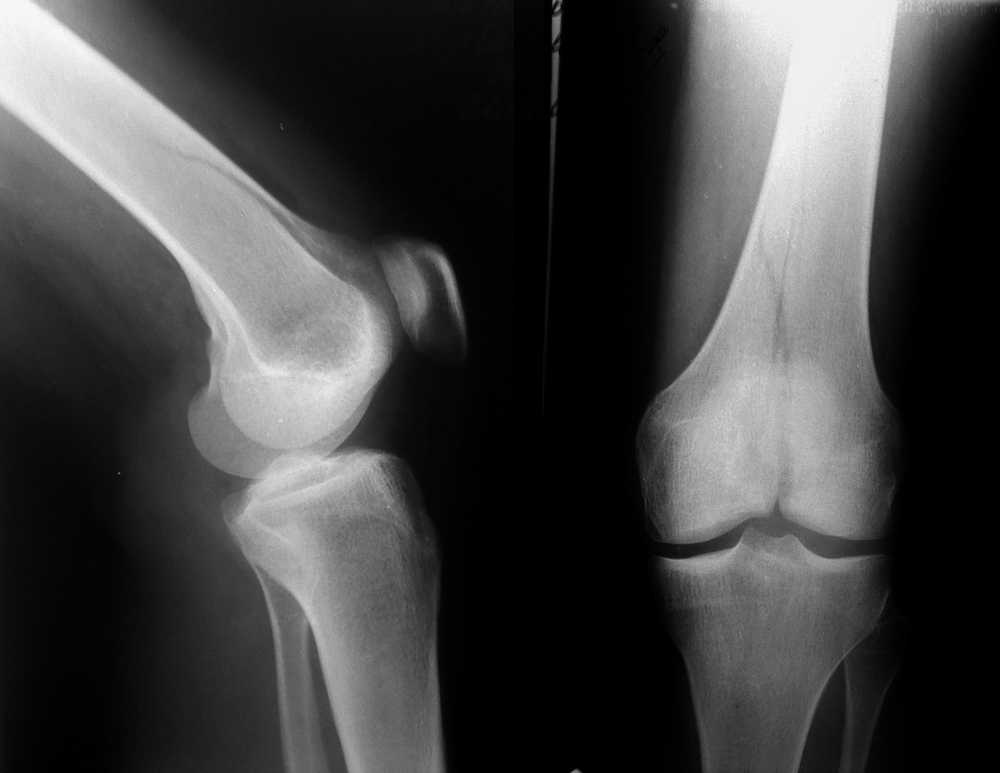

Межмыщелковый перелом бедра

Перелом медиального мыщелка правой бедренной кости, по классификации Мюллера - 33-В2.1

Женщина, 24 года, травма в быту, при падении с лестницы на согнутое колено.

Кожные покровы в хорошем состоянии, гемартроз умеренный, повреждения крестообразных связок пока не видно.

Вопрос стоит в следующем - достаточно-ли пары спонгиозных винтов и добавочной обычной длинной тонкой Г-образной пластины (это все есть в больнице) или обязательно ставить мыщелковую пластина для бедра, на всю длину перелома?